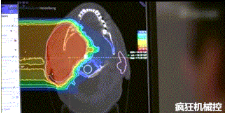

光柵掃描被集成到360°重離子治療一體機(jī)中,這種極其精確的照射方法以毫米為單位掃描腫瘤,可以保護(hù)健康組織且只治療腫瘤區(qū)域。

特別是腫瘤在高度輻射敏感位置或者諸如視神經(jīng)附近的復(fù)雜位置,可以通過(guò)選擇最佳射束入射角來(lái)減小這些器官的損傷。